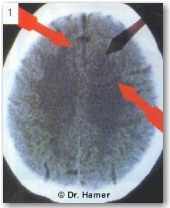

Во время этой первой фазы исцеления НН на томографическом снимке проявляется в виде темных концентрических колец (что указывает на наличие отека в этой части мозга).

Пример: на данном снимке виден НН в ПКЛ-фазе А, соответствующий опухоли легких, указывающий на разрешённый «конфликт страха смерти». Большинство подобных «конфликтов страха смерти», приводящих к раку легких, вызываются постановкой неблагоприятного диагноза с негативным прогнозом.